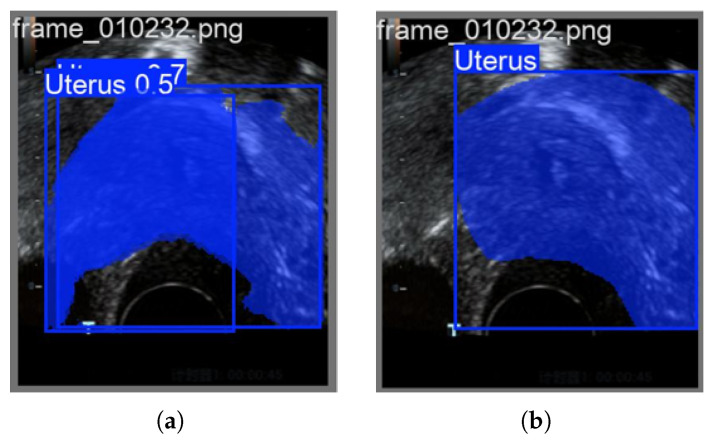

准确识别子宫内膜区域是早期发现子宫内膜病变的关键。然而,目前的检测模型在处理子宫内膜成像数据时仍然面临两大挑战:(1)在复杂和嘈杂的环境中,识别精度仍然有限,部分原因是图像中颜色信息的利用不足;(2)传统的基于二维pca (2DPCA-based)的特征选择方法在捕获和表达子宫内膜区域关键特征方面能力有限。为了解决这些问题,本文提出了一种新的算法,称为特征级图像融合和改进的群体智能优化算法(FLFSI),该算法将学习引导的二进制粒子群优化(BPSO)策略与图像特征选择和重建框架相结合,以增强临床超声图像中子宫内膜区域的检测。具体而言,FLFSI有助于提高特征选择精度和图像重建质量,从而提高区域识别任务的整体性能。首先,我们通过结合结构和颜色信息的特征工程技术增强子宫内膜图像表征,从而提高重建质量并强调关键区域特征。其次,将BPSO算法引入特征选择阶段,提高了特征选择的准确性和全局搜索能力,同时有效降低了冗余特征的影响。在此基础上,对BPSO设计进行了改进,提高了算法的收敛速度和优化效率。本文提出的FLFSI算法可以集成到主流的检测模型中,如YOLO11和YOLOv12。当应用于YOLO11时,FLFSI达到96.6%的Box mAP和87.8%的Mask mAP。利用YOLOv12,进一步将Mask mAP提高到88.8%,表现出优异的跨模型适应性和鲁棒性检测性能。大量的实验结果验证了FLFSI在增强子宫内膜区域检测用于临床超声图像分析方面的有效性和广泛适用性。

Accurate identification of the endometrial region is critical for the early detection of endometrial lesions. However, current detection models still face two major challenges when processing endometrial imaging data: (1) In complex and noisy environments, recognition accuracy remains limited, partly due to the insufficient exploitation of color information within the images; (2) Traditional Two-dimensional PCA-based (2DPCA-based) feature selection methods have limited capacity to capture and represent key characteristics of the endometrial region. To address these challenges, this paper proposes a novel algorithm named Feature-Level Image Fusion and Improved Swarm Intelligence Optimization Algorithm (FLFSI), which integrates a learning guided binary particle swarm optimization (BPSO) strategy with an image feature selection and reconstruction framework to enhance the detection of endometrial regions in clinical ultrasound images. Specifically, FLFSI contributes to improving feature selection accuracy and image reconstruction quality, thereby enhancing the overall performance of region recognition tasks. First, we enhance endometrial image representation by incorporating feature engineering techniques that combine structural and color information, thereby improving reconstruction quality and emphasizing critical regional features. Second, the BPSO algorithm is introduced into the feature selection stage, improving the accuracy of feature selection and its global search ability while effectively reducing the impact of redundant features. Furthermore, we refined the BPSO design to accelerate convergence and enhance optimization efficiency during the selection process. The proposed FLFSI algorithm can be integrated into mainstream detection models such as YOLO11 and YOLOv12. When applied to YOLO11, FLFSI achieves 96.6% Box mAP and 87.8% Mask mAP. With YOLOv12, it further improves the Mask mAP to 88.8%, demonstrating excellent cross-model adaptability and robust detection performance. Extensive experimental results validate the effectiveness and broad applicability of FLFSI in enhancing endometrial region detection for clinical ultrasound image analysis.